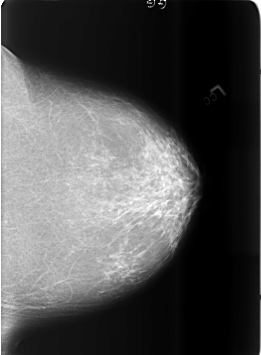

ics_version 1.0 filename B-3465-1 DATE_OF_STUDY 12 5 1998 PATIENT_AGE 67 FILM FILM_TYPE REGULAR DENSITY 2 DATE_DIGITIZED 7 4 1999 DIGITIZER LUMISYS LASER SEQUENCE LEFT_CC LINES 5680 PIXELS_PER_LINE 4176 BITS_PER_PIXEL 12 RESOLUTION 50 NON_OVERLAY LEFT_MLO LINES 5704 PIXELS_PER_LINE 4152 BITS_PER_PIXEL 12 RESOLUTION 50 NON_OVERLAY RIGHT_CC LINES 5696 PIXELS_PER_LINE 4088 BITS_PER_PIXEL 12 RESOLUTION 50 OVERLAY RIGHT_MLO LINES 5712 PIXELS_PER_LINE 4104 BITS_PER_PIXEL 12 RESOLUTION 50 OVERLAY |